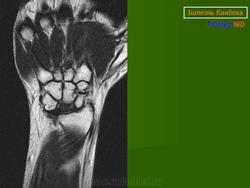

Остеохондропатия полулунной кости кисти (болезнь Кинбека), (Osteochondropathia ossis scaphoidei manus)

Заболевание впервые описано австрийским рентгенологом Кинбеком (1910). В основе патологии лежит субхондральный некроз полулунной кости запястья. Наблюдается преимущественно у лиц мужского пола в возрасте от 17 до 40 лет, подверженных частым повторным травмам кисти. Играет значение и постоянное перенапряжение кисти в процессе интенсивного ручного труда у слесарей, токарей, плотников, столяров. Процесс чаще локализуется на правой руке.

При рентгенологическом исследовании в ранней стадии заболевания отмечается смазанная картина структурного рисунка полулунной кости. Со временем тень ее становится более интенсивной по сравнению с соседними костями запястья, размеры уменьшаются, появляется неровность контуров, могут возникать кистозные изменения. В дальнейшем развивается фрагментация, сплющивание и прогрессирующая деформация полулунной кости, которая часто приобретает треугольную форму. Смежные суставные щели при этом расширяются. В редких случаях происходит уменьшение размеров полулунной кости с явлениями повышенного склероза костной ткани, напоминающего мраморную болезнь. В позднем периоде заболевания рентгенологически определяются явления остеоартроза.

Остеохондропатия полулунной кости

Болезнь Кинбека